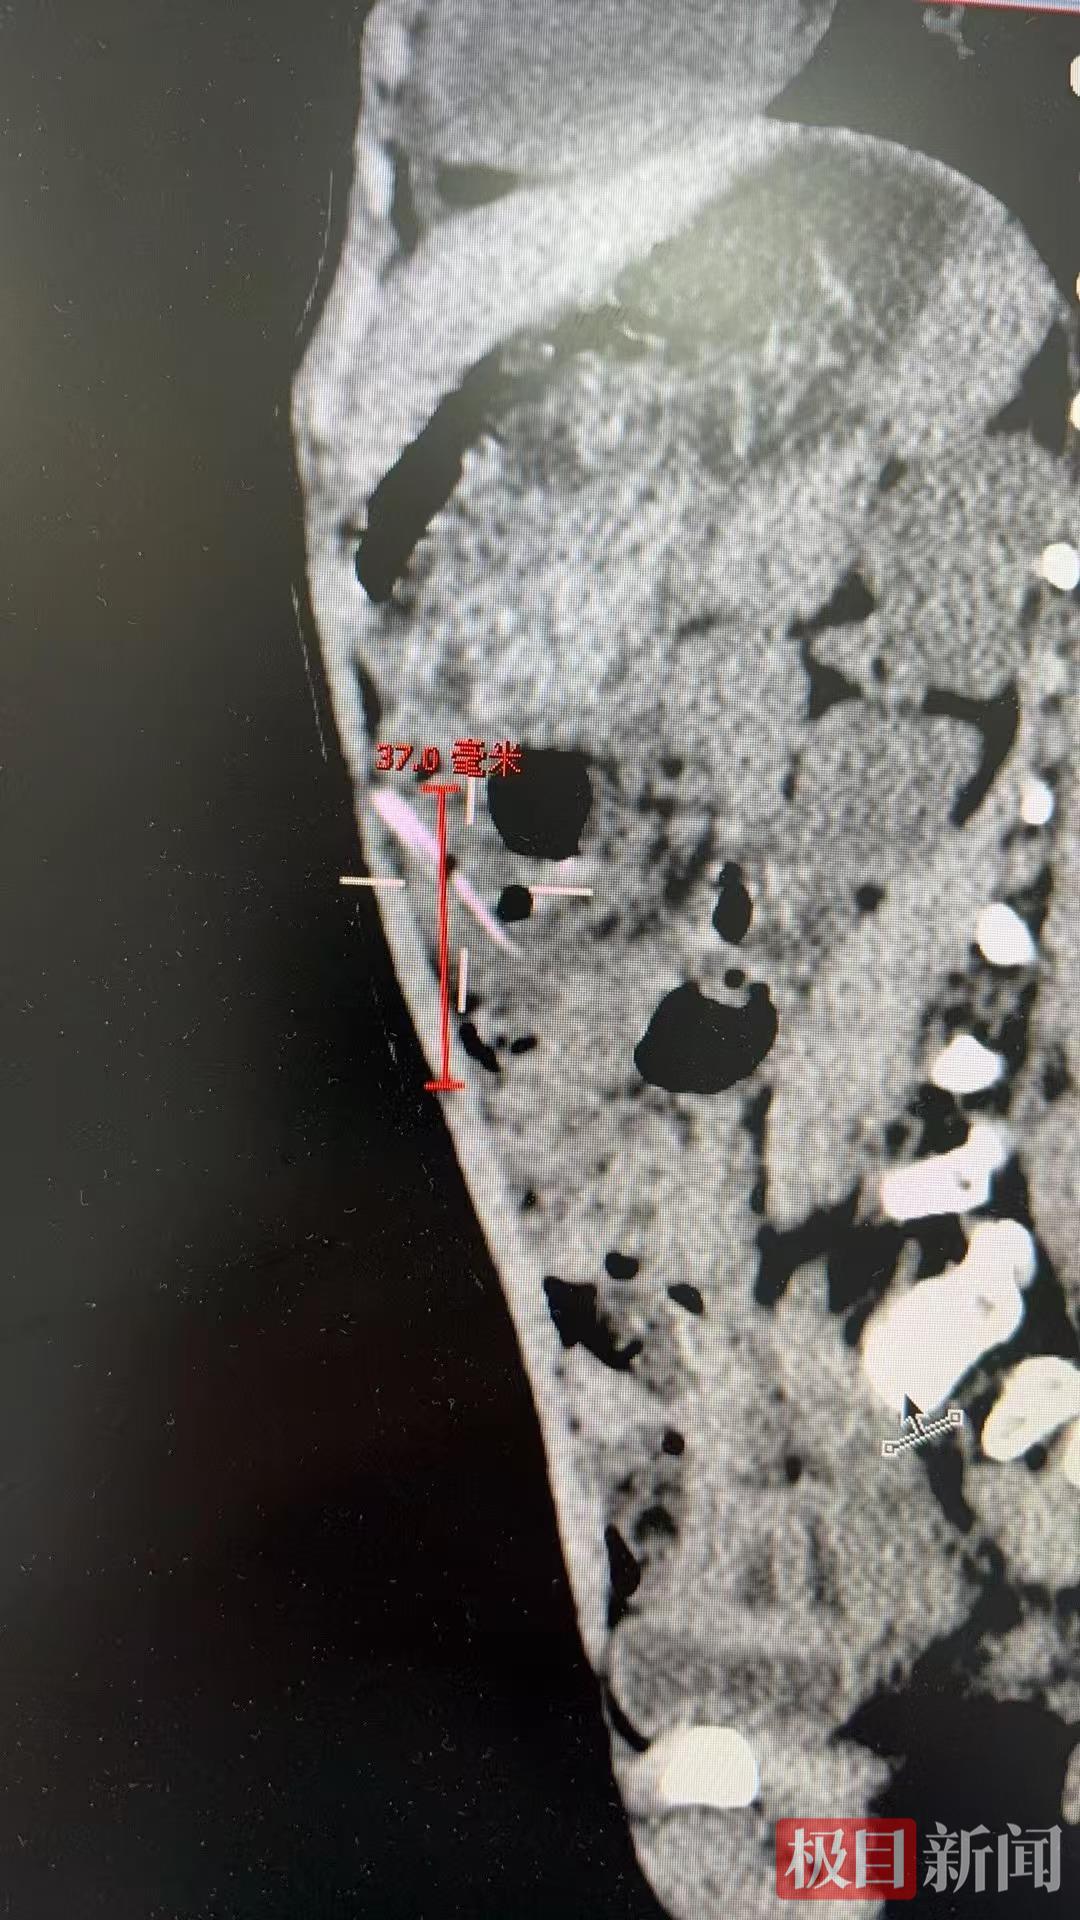

儿童普通外科副主任张伊凡听添添父母讲述了病史,查看孩子并无感冒症状,推测腹痛很有可能与误食异物有关,随后的腹部CT检查发现孩子腹腔内疑似存在约2.5厘米的异物,张伊凡立刻将孩子收入院。

为了避免延误治疗,在征得家长同意后,医生为添添实施了腹腔镜微创手术。术中探查结果令人心惊:一根长约2-3厘米的尖锐竹签,已穿透患儿肠管,深深刺入腹腔。万幸的是,竹签未伤及其他重要脏器,也未引发严重感染。